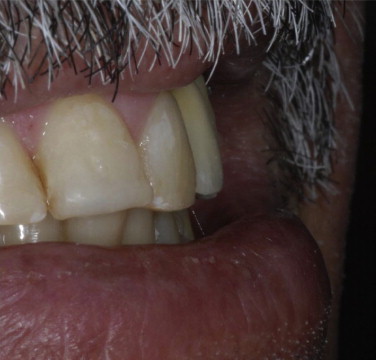

Fig. 11.

Right buccal view of the clinical aspect after the case finalization.